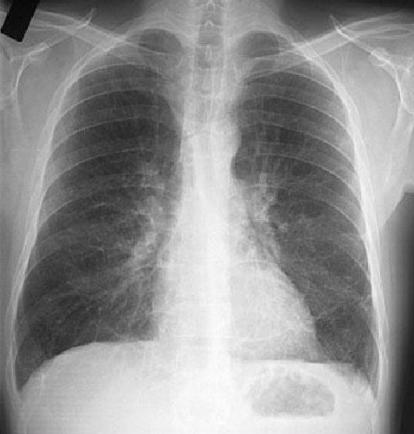

1、X线:病情较轻时仅表现为肺纹理增粗,病情加重时双肺可见环状透光阴影,呈卷发状或蜂窝状,常伴肺段或肺叶不张及炎症浸润阴影。

早期支气管扩张,双肺纹理增多、增粗。